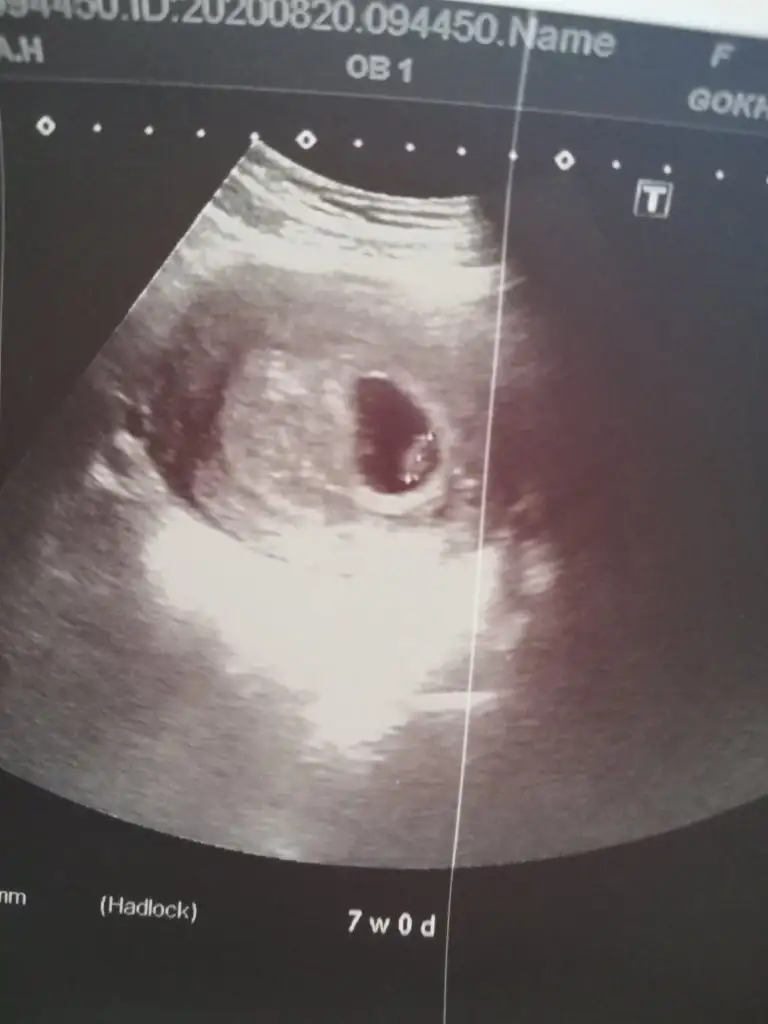

Kızlar bebeğimi gördüm şükürler olsun kalbi pıt pıt darısı görmeyenlere inşallah sağ sağlim alırız kucağımıza miniklerimizi. Bir tek benim tsh sınırdaymış ama şimdilik dahiliyeye göndermiycem dedi

Maşallah benimki ile çok benziyor görüntüsü benim de 7+1 di. Gözünüz aydın şu kadarcık görüntü bile insanı kendinden geçiriyor değil mi? Allah herkese sağlıkla nasip etsin..

Benim normal de 7+2 ama ultrasonda 7+0 çıktı ama doktor her şey çok güzel ddi. Aynen minicik şey bile dünyalar kadar mutlu ediyor insanı 2 hafta sonra tekrar çağırdı sizi de çağırdı mı?